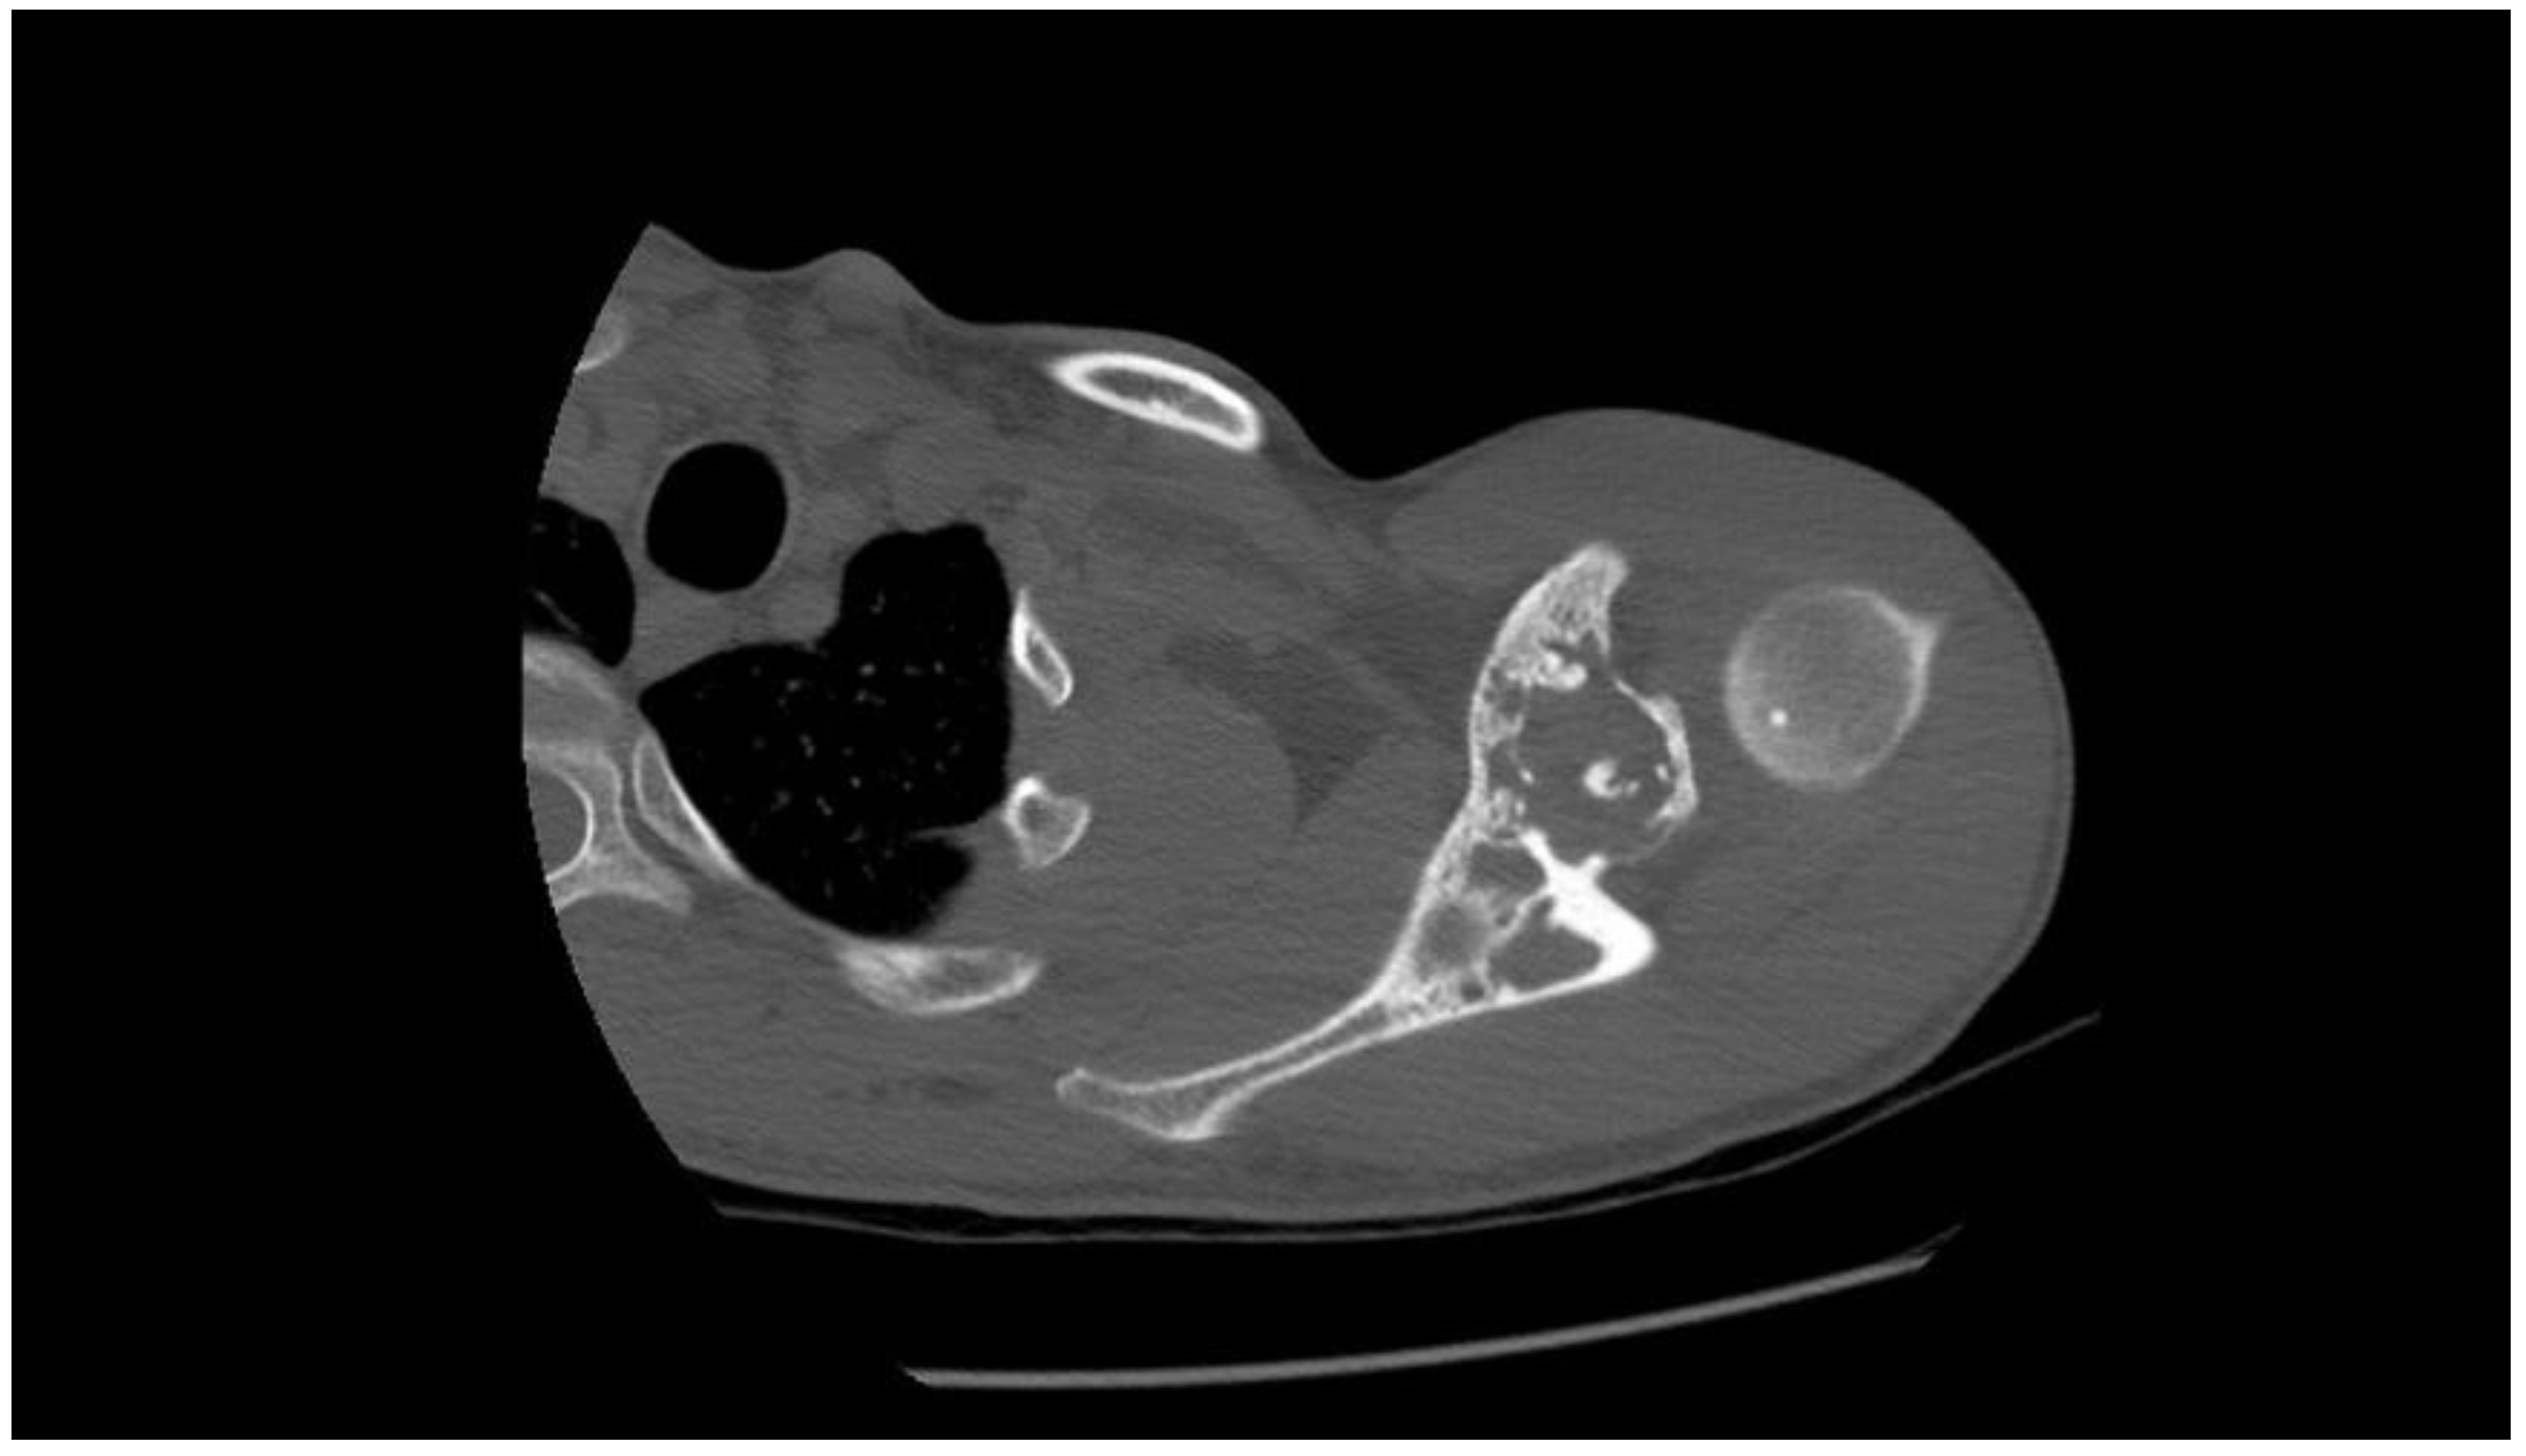

2. Detailed Case Description

2.1. Oncological Staging

2.2. Prostheses Project